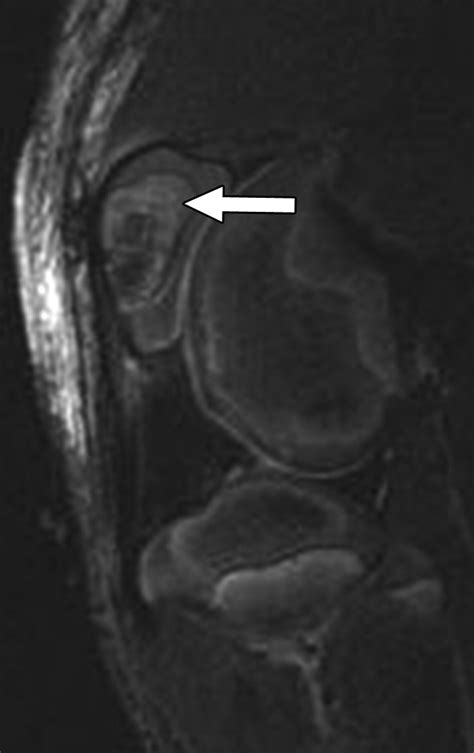

While an X-ray can easily detect a fracture, a bone contusion is often invisible on standard X-ray imaging. Because the structural integrity of the bone remains intact, X-rays often come back "normal," which can lead patients to believe their injury is minor. Instead, physicians typically use Magnetic Resonance Imaging (MRI) to visualize the edema or swelling within the bone marrow, which is the hallmark of a contusion.